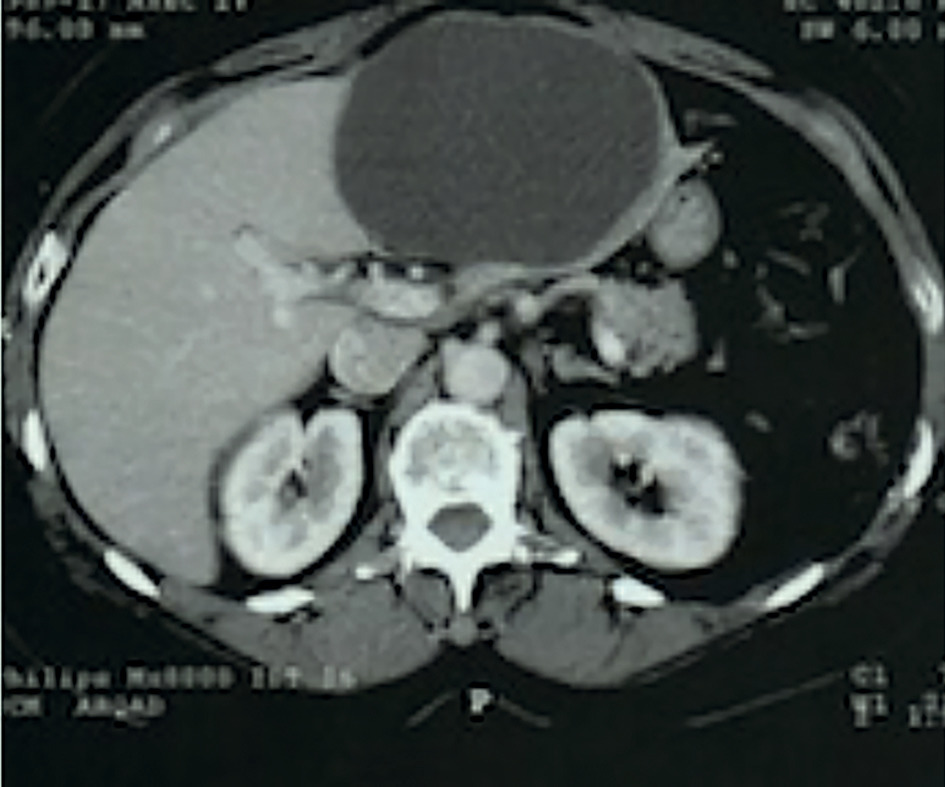

Cette masse augmentant rapidement, avec intensification des douleurs et apparition d’une gêne à l’inspiration, un scanner abdominal avec injection est demandé en urgence. Il confirme un volumineux kyste liquidien occupant tout le segment hépatique n° III (fig. 2 ).

Cette masse augmentant rapidement, avec intensification des douleurs et apparition d’une gêne à l’inspiration, un scanner abdominal avec injection est demandé en urgence. Il confirme un volumineux kyste liquidien occupant tout le segment hépatique n° III (